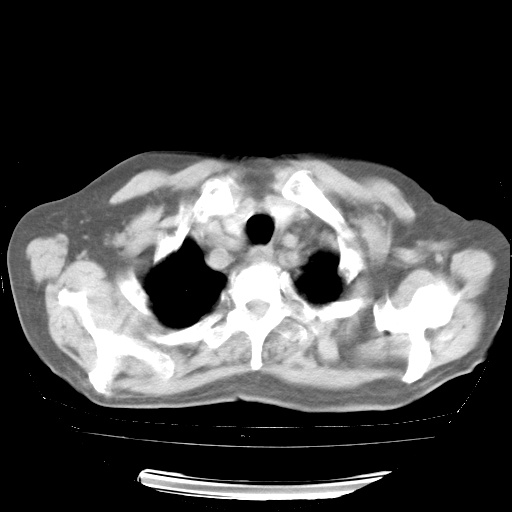

4月28日肺部CT——再次出现类似去年5月9日——透光度降低,“间质性”改变。

4月28日肺部CT——再次出现类似去年5月9日——磨玻璃样、间有“粟粒样”改变。

4月28日肺部CT